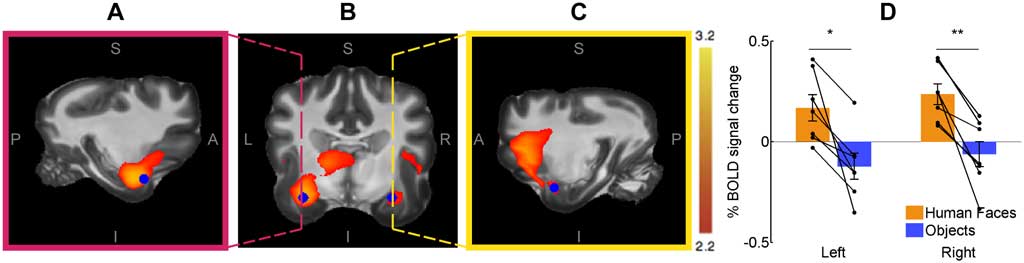

Se utilizó un paradigma de estimulación visual con diseño de bloques para comparar la actividad provocada por rostros humanos en comparación con objetos cotidianos. El resultado es que la actividad cerebral relacionada con la percepción de los rostros humanos cambió significativamente en varias regiones del cerebro, pero principalmente en la corteza temporal bilateral.

En el contraste opuesto (es decir, los objetos cotidianos contra las caras humanas) no mostraron cambios significativos actividad cerebral. La corteza temporal es parte de la vía visual ventral, y los resultados de estos experimentos son consistentes y coherentes con los informes de otras especies como primates y ovejas, que sugieren un alto grado de conservación evolutiva de esta vía para el procesamiento de la cara.

Este estudio de Laura V. Cuaya, Raúl Hernández-Pérez y Luis Concha, presenta la corteza temporal como principal candidato para procesar rostros humanos, un pilar importante de la cognición social en los perros.